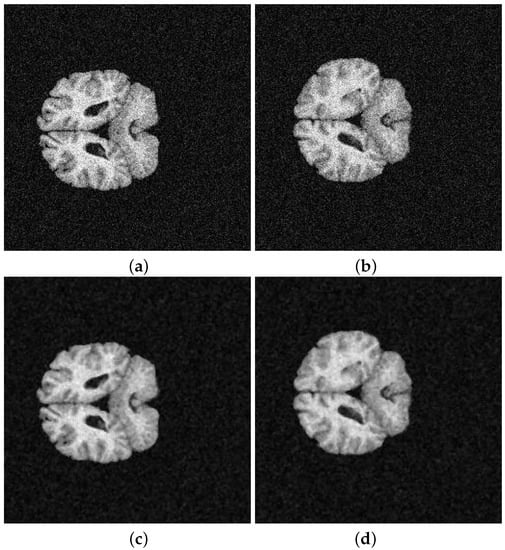

| K-means | FCM | SFCM | KFCM | |

|---|---|---|---|---|

| K | 4, 6, 8, 10 | 4, 6, 8, 10 | 4, 6, 8, 10 | 4, 6, 8, 10 |

| m | - | 1.0, 1.5, 2.0 | 1.0, 1.5, 2.0 | 1.0, 1.5, 2.0 |

| p | - | - | 1.0, 2.0 | - |

| q | - | - | 1.0, 2.0 | - |

| r | - | - | 2.0, 3.0, 4.0 | - |

| - | - | - | 1, 3, 5 | |

| - | - | - | average, median, weighted |